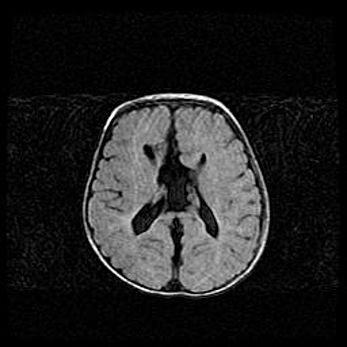

Сообщающаяся гидроцефалия. Кистозная энцефаломаляция головного мозга.

Возраст: 3 месяца 4 дня

Вес: 3100 г

Пол: женский

Окружность головы: 34 см

Срок гестации: 31 неделя

Кистозная энцефаломаляция головного мозга - одна из форм поражения головного мозга в детском возрасте. Характеризуется возникновением множественных и распространённых кист в коре, белом веществе и подкорковых образованиях головного мозга у плодов, новорождённых и детей раннего возраста. Развитие кистозной энцефаломаляции связано с внутриутробной асфиксией и гипотонией, родовой травмой, тромбозом синусов, пороками развития сосудов, инфекциями, сепсисом и другими причинами. Наиболее значимые инфекционные агенты: вирусы простого герпеса, цитомегалии, краснухи, токсоплазмы, энтеробактерии, золотистый стафилококк и другие.